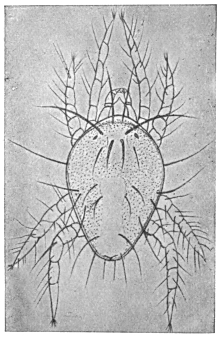

102Sarcocystis miescheriana in muscle of pig. (After Kühn)188

103

104Sarcocystis miescheriana, mature trophozoite189

105Sarcocystis tenella in section, as seen in œsophagus of sheep190